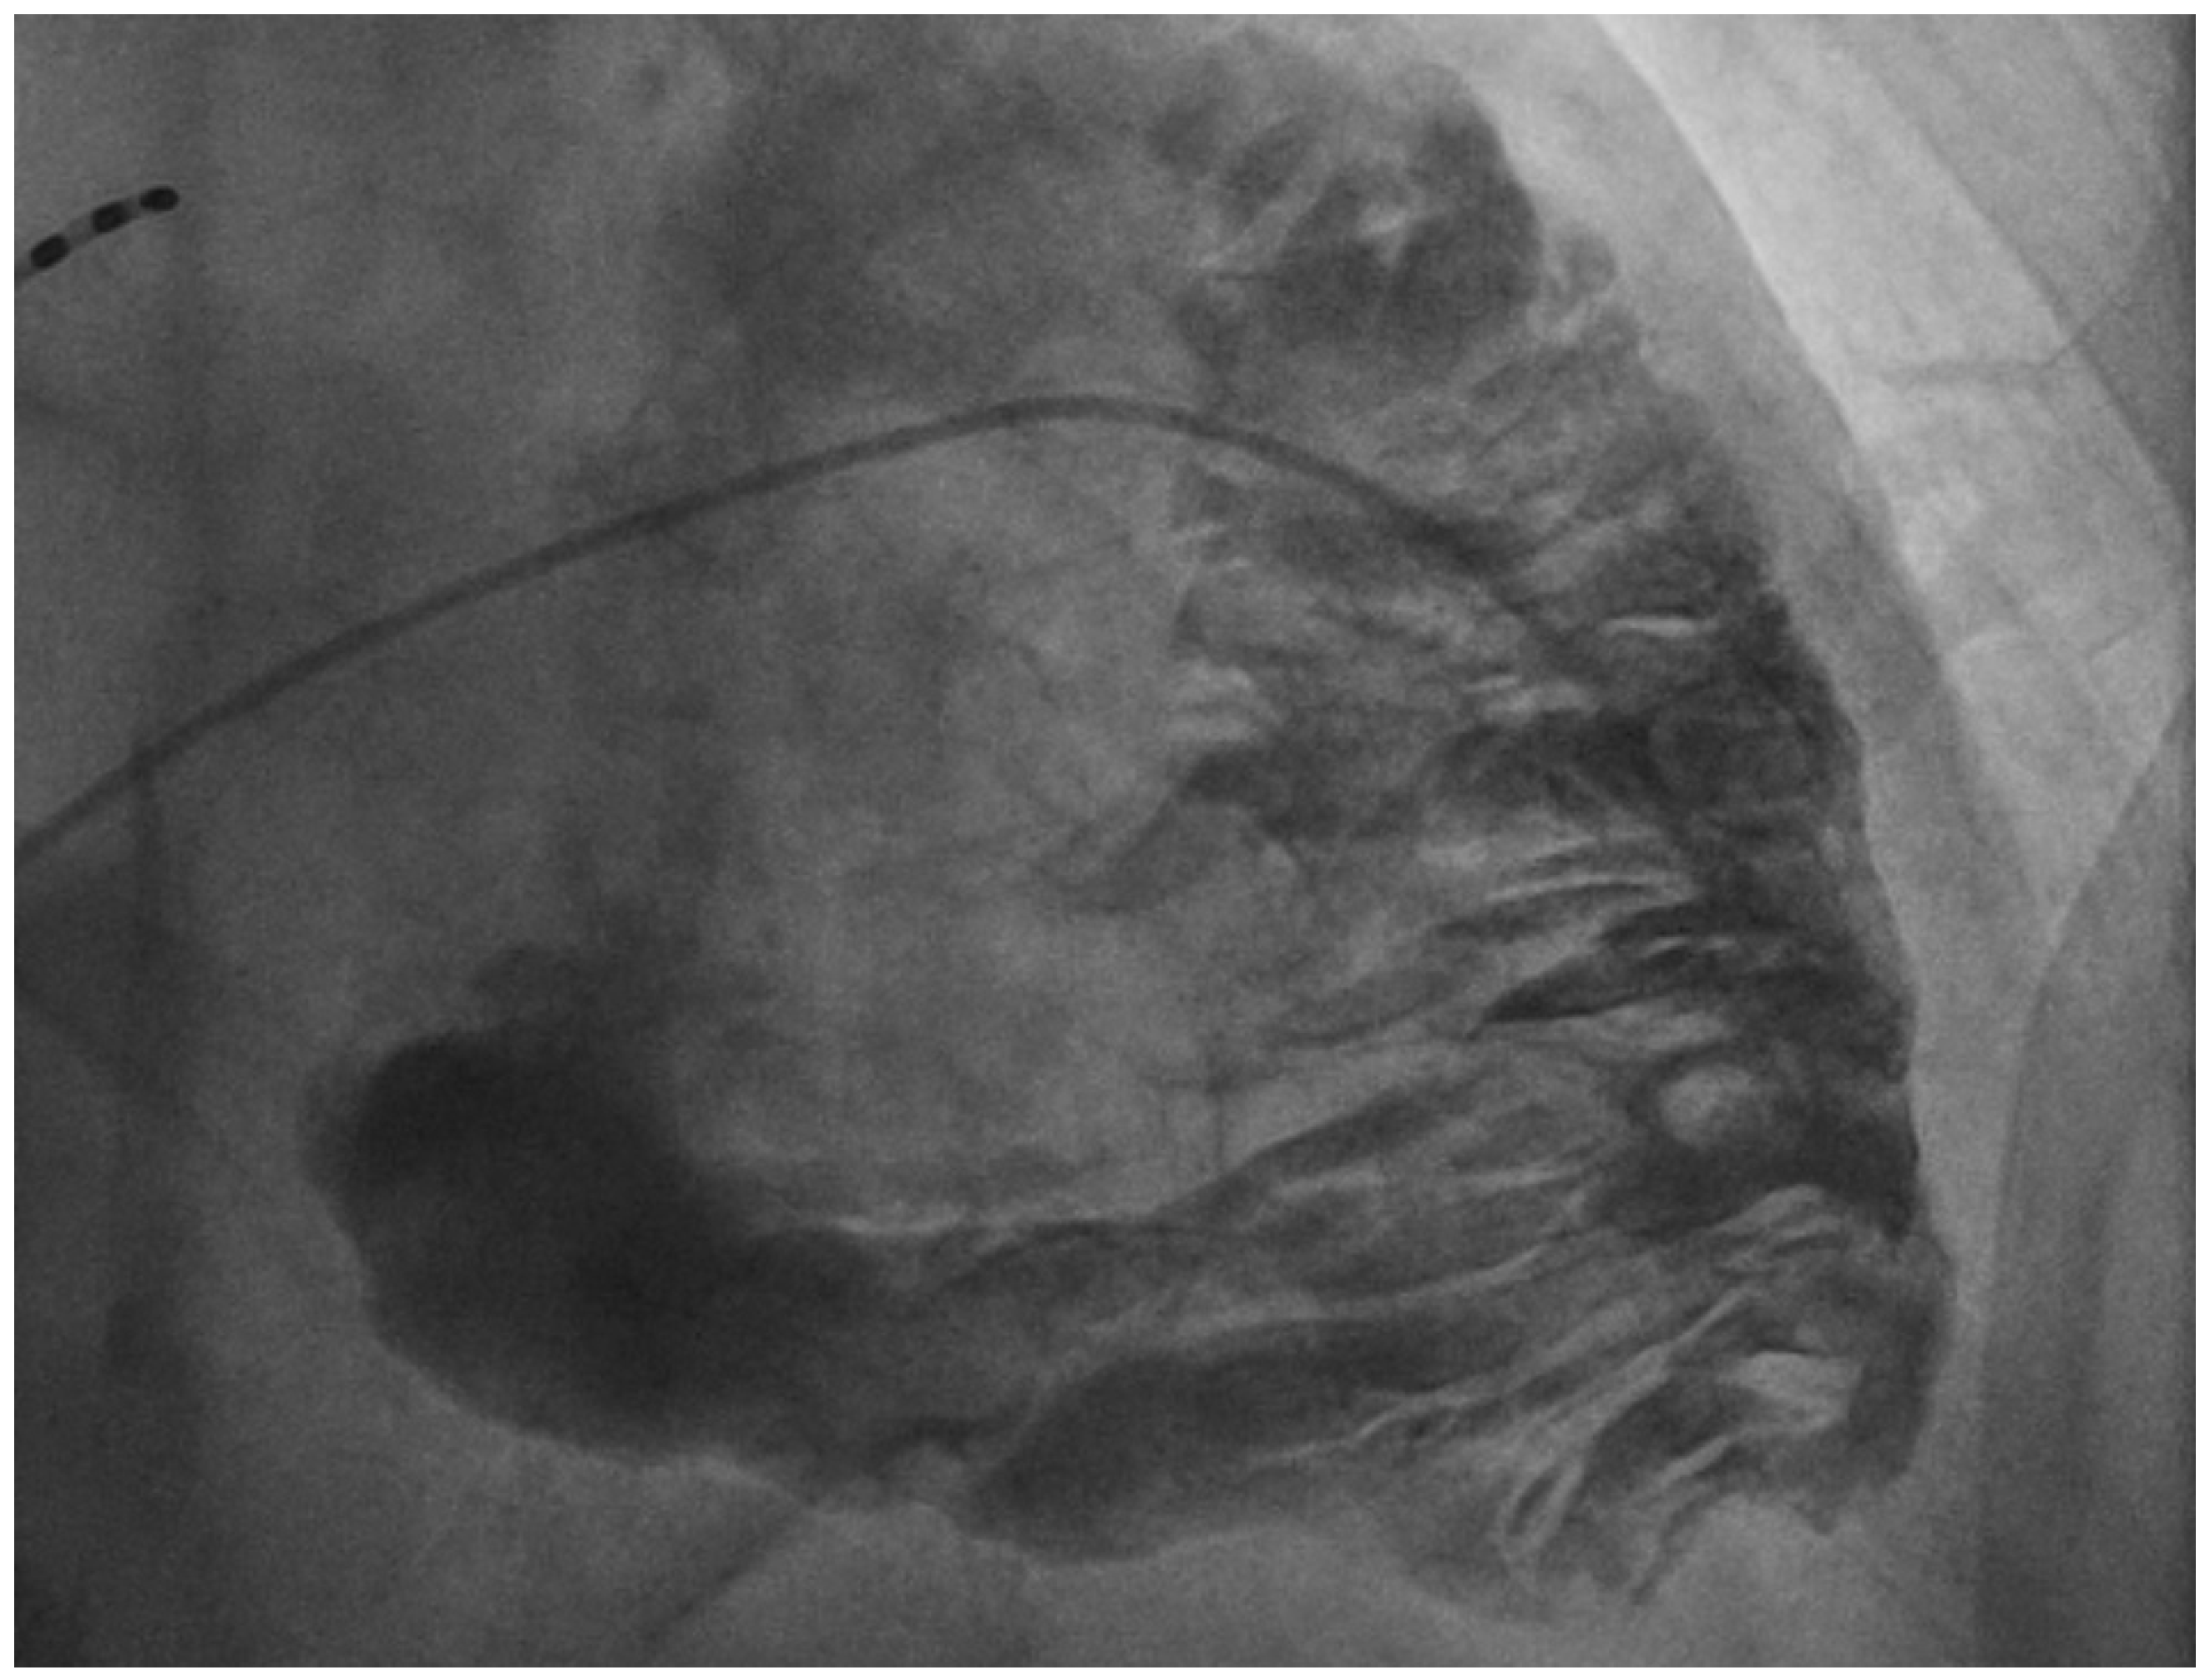

Figure 1. Right ventricular angiography showing dilatation of the right ventricle with akinetic/dyskinetic bulgings, creating the “pile d’assiettes” image suggestive of arrhythmogenic right ventricular cardiomyopathy. A 76-year-old male patient with past history of chronic obstructive pulmonary disease, right iliac artery stenting, dyslipidaemia, high blood pressure and previous smoking, presented to the emergency department of our institution with chest tightness, signs and symptoms of acute decompensated right heart failure and presyncope episodes. Upon admission, his electrocardiogram (ECG) showed sustained monomorphic ventricular tachycardia at 180 bpm, with left bundle branch morphology and a superior axis, which was electrically cardioverted, and the patient was subsequently admitted to the intensive care unit. The troponin (601 ng/L) and NTproBNP (24,019 ng/L) levels were elevated, the echocardiography showed a very dilated right ventricle (RV) (a diameter of the RV outflow track in end-diastole of 44 mm in parasternal short axis view) with global systolic dysfunction and akinetic anterior and lateral walls. The coronary angiography was normal. The cardiac magnetic resonance (CMR) confirmed global RV dysfunction with regional akinesia and aneurysms and showed signs of fibro-fatty replacement of the RV myocardium. There were no left ventricular abnormalities identified by echocardiography or CMR. Furthermore, the ECG after cardioversion showed inverted T waves and an epsilon wave in V1-V3 leads, in the absence of right bundle branch block and late potentials by signal-averaged ECG. As such, the patient presented criteria for the diagnosis of arrhythmogenic right ventricular cardiomyopathy (ARVC) as described by the 2020 “Padua Criteria” for the diagnosis of ARVC [1], recently revised by the 2024 European Task Force consensus report [2]. However, he presented no familial history of ARVC, was 76 years of age at the time of diagnosis and was asymptomatic until now. Given these considerations, we performed a right ventricular angiography which showed dilatation of the RV with akinetic/dyskinetic bulging, creating the “pile d’assiettes” image suggestive of ARVC (Video S1). The RV angiography has a diagnostic specificity of more than 90% [3] and was considered the gold standard diagnostic exam for ARVC, particularly before the era of advancements in cardiac magnetic resonance imaging [4], while more recent studies on this subject are sparse. In the case of this patient, the RV angiography contributed to establish a diagnosis of ARVC with a very late presentation, to our knowledge the latest presentation in terms of age described in the literature. Subsequently, the patient was implanted with a defibrillator, and his family benefited from screening.

The following supporting information can be downloaded at: https://www.mdpi.com/article/10.3390/diagnostics14131434/s1, Video S1: Right ventricular angiography showing dilatation of the right ventricle with akinetic/dyskinetic bulgings, creating the “pile d’assiettes” image suggestive of arrhythmogenic right ventricular cardiomyopathy.